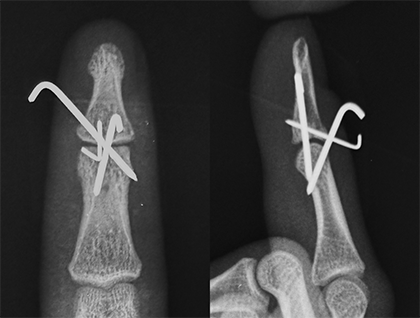

手術は局所麻酔を行い、金属ピンなどを用いて折れた骨や指の第一関節を固定します(図8,9,10,11)。装具を用いた固定を行った場合も手術を行った場合も、約6週間の終日固定が必要となります。また、固定期間中は装具の装着状況や指の状態を評価するため、定期的な通院が必要となります。

図9.2本の金属ピンで治療を行いました

図11.3本の金属ピンで治療を行いました